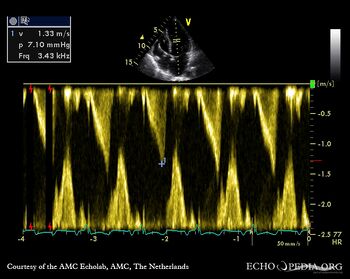

E00510.jpg

Continuous-wave doppler signal: dynamic gradient in the middle of left ventricle